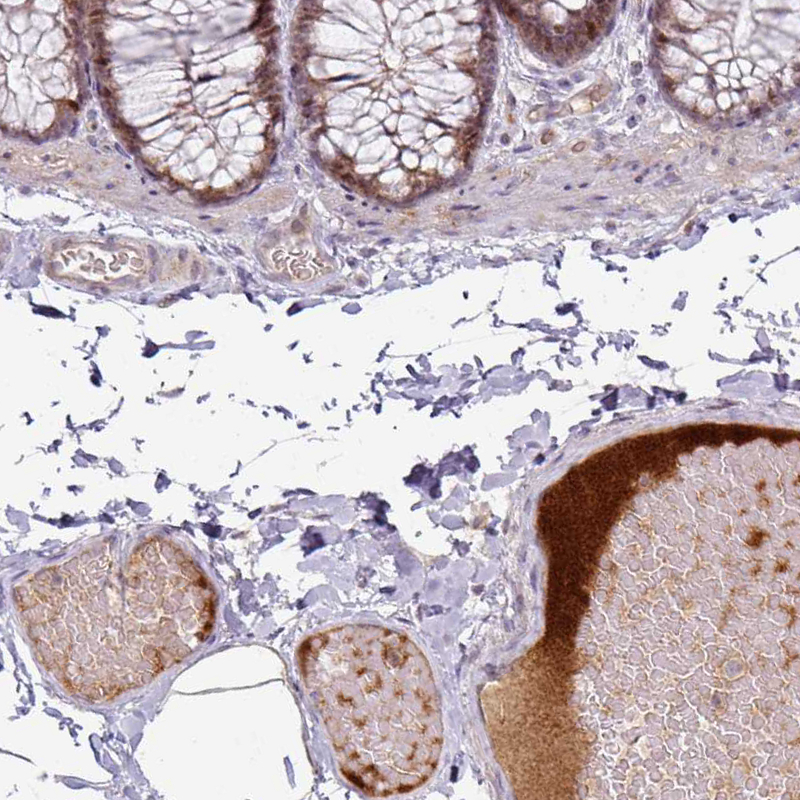

Immunohistochemical staining of human urinary bladder shows moderate positivity in plasma in blood vessels.